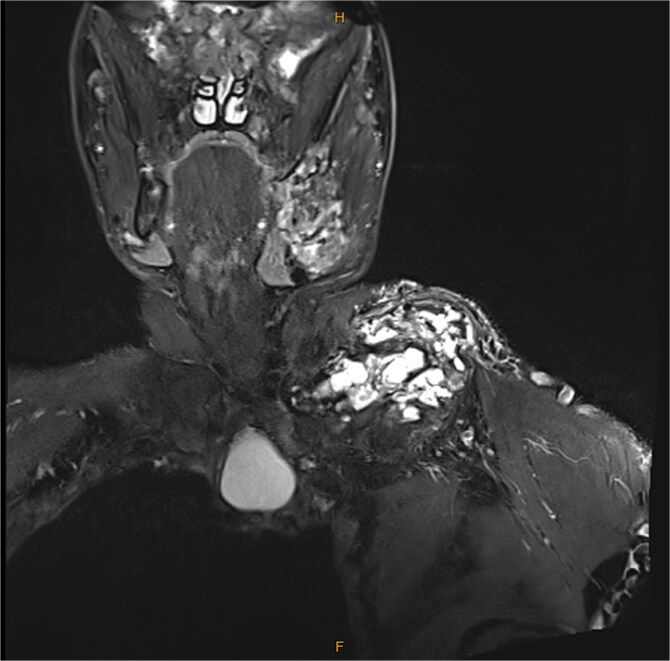

麦丘内-奥尔布赖特综合征(MAS)是一种罕见的马赛克疾病,其特征是典型的骨纤维发育不良(FD)、卡氏皮肤斑疹和功能亢进的内分泌疾病。MAS是由g蛋白α亚基(GNAS)基因的合子后突变导致g蛋白α亚基体细胞活化引起的。目前还没有批准的治疗MAS的方法。我们报告了一例43岁男性木匠,患有严重的多牙性FD和成人发作的生长激素(GH)过量,他接受了denosumab和生长抑素类似物的治疗,并诊断为慢性髓性白血病(CML)。患者有多处骨骼病变,导致运动疼痛和左臂神经血管受损。前肢截肢被认为是治疗锁骨大病变,然而,累及他的胸廓导致严重的心肺损伤,包括限制性肺疾病,手术被认为风险太大。在静脉注射双膦酸盐治疗疼痛失败后,开始使用Denosumab,从而减轻疼痛。内分泌病变筛查显示生长激素过量,胰岛素样生长因子-1 (IGF-1)水平升高,垂体腺瘤7mm。Lanreotide开始作为药物治疗,导致IGF-1水平降低。在denosumab治疗9个多月后,患者在常规全血检查中被诊断为CML。患者使用伊马替尼后血液学得到缓解。多骨不全可导致严重的骨骼畸形并发症,包括心肺并发症。本病例为重度MAS/FD患者,诊断为CML。我们假设CML不太可能是由于MAS引起的,因为两者具有不同的致病途径。Denosumab在疼痛管理方面是有效的,然而,它应该谨慎使用,并且没有大型研究来指导长期管理。MAS的评估和管理还应包括详细的内分泌病变评估和筛查,即使在成年期也是如此。

McCune-Albright syndrome (MAS) is a rare mosaic disorder characterized by the classic triad of fibrous dysplasia of bone (FD), café-au-lait skin macules, and hyperfunctioning endocrinopathies. MAS is caused by a postzygotic mutation in the G-protein alpha subunit (GNAS) gene resulting in G-protein α-subunit somatic activation. There is no approved treatment for MAS. We present the case of a 43-yr-old male carpenter with severe polyostotic FD and adult-onset growth hormone (GH) excess who was treated with denosumab and somatostatin analog, complicated with a diagnosis of chronic myeloid leukemia (CML). The patient had multiple skeletal lesions, resulting in pain on movement and neurovascular compromise of the left arm. A forequarter amputation was considered to treat a large clavicular lesion, however, involvement of his thoracic cage resulted in significant cardiopulmonary impairment, including restrictive lung disease, and the surgery was deemed too risky. Denosumab was commenced after failed intravenous bisphosphonate for pain management, resulting in alleviation of pain. Screening of endocrinopathy revealed GH excess with an elevated Insulin-like Growth Factor-1 (IGF-1) level and 7 mm pituitary adenoma. Lanreotide was commenced as a medical therapy, resulting in a reduction in IGF-1 levels. Over 9 mo into the denosumab treatment, the patient was diagnosed with CML in the context of routine full blood examination. The patient achieved a hematological remission with imatinib. Polyostotic FD can lead to serious complications from deformities of the skeleton, including cardiopulmonary complications. This case represents a patient with a severe spectrum of MAS/FD with a diagnosis of CML. We postulate that CML is unlikely due to the MAS, as the two have different pathogenic pathways. Denosumab is effective in pain management, however, it should be used with caution, and there are no large studies to guide long-term management. Evaluation and management of MAS should also include detailed endocrinopathy assessment and screening, even in adulthood.